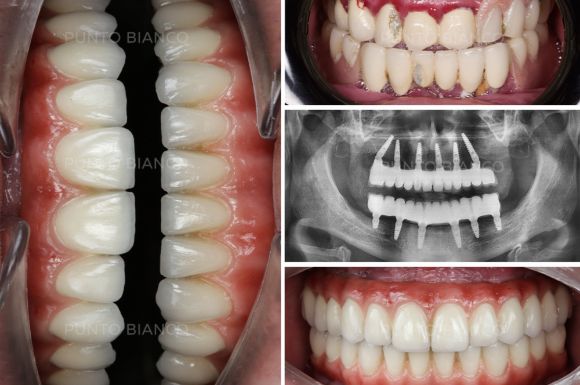

Implanturile dentare All-on-X reprezintă o revoluție în domeniul stomatologiei, oferind o soluție eficientă și permanentă pentru pacienții care se confruntă cu pierderea majorității sau a tuturor dinților pe o arcadă dentară. Această tehnologie avansată permite restaurarea întregii arcade dentare utilizând un număr minim de implanturi (de obicei 4 sau 6), strategic plasate pentru a asigura stabilitate și confort maxim.

Suntem printre puținele clinci stomatologice din Moldova care promit și chiar realizează atât inserarea implanturilor cât și dantura fixă provizorie în ziua intervenției sau a doua zi. Aceasta este posibil datorită tehnologiilor avansate de care dispunem în clinica Punto Bianco (amprente digitale realizate cu cel mai performant scaner intraoral, tomografii 3D direct in clinică, propiul laborator digital) dar și echipei multidisciplinare cu o experiență mare în reabilitări complete și complexe a danturii.